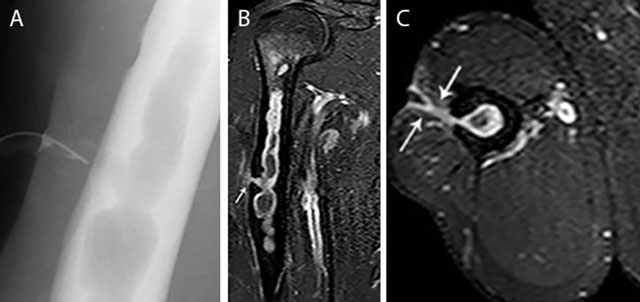

Figure 13

Chronic osteomyelitis of the right humerus with fistula formation. Plain radiograph (sinography) (a), coronal (b) and axial (c) Fat–Sat T1–WI after gadolinium contrast administration. The sinography (a) shows an intramedullary well defined lytic lesion with scalloping of the cortex. Note the presence of a catheter in the sinus. There is enhancement of the wall of the intra-osseous abscess and the wall of the fistula (white arrow) (b, c). Image courtesy Dr. H. Declercq, Dendermonde.